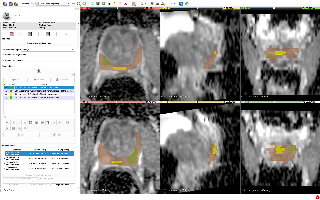

心脏

EchoNet

| 名称 | 标注内容 | 类型 | 模态 | 数量 | 标签格式 | 文件格式 |

|---|---|---|---|---|---|---|

| EchoNet | 心脏 | 分割 | MRI | 10300 | 0/1 |

介绍论文: EchoNet-Dynamic: a Large New Cardiac Motion Video Data Resource for Medical Machine Learning

MMWHS

| MMWHS | 心脏 | 分割 | CT / MRI | 20CT、20MRI | 类别 | nii |

mmwhs是心脏分割数据集,共有8类,MRI和CT两种模态 相关项目: Hybrid Loss Guided Convolutional Networks for Whole Heart Parsing